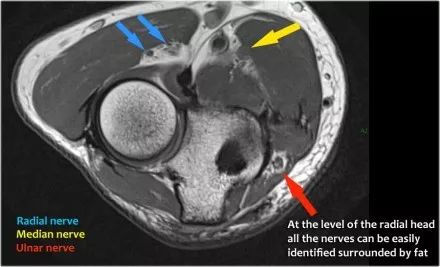

桡神经:在桡骨头水平可以最好地识别桡神经,在那里你可以看到桡骨隧道中的浅表和深支(箭头)。这是寻找桡神经的非常一致的地方。

深分支形成后骨间神经,穿过Frohse拱门(箭头)的旋后肌。

在下图可以看到,在左上方T1W图像中,伸肌中存在高信号脂肪,肌肉体积减少,这表明脂肪萎缩。右上方的轴向图像显示了旋后肌中更近端的质量。

矢状图像证实这是脂肪瘤。因此萎缩是骨间后神经受压的结果,骨间后神经是桡神经的一个分支。